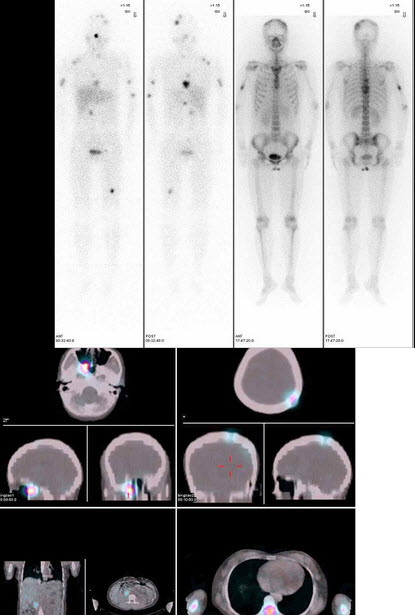

女性,32岁,妊娠期间发现高血压,24h尿VMA多次偏高,行I-MIBG全身显像及ECT/CT图像融合如图,正确的诊断是()

A.球后异位嗜铬细胞瘤

B.恶性嗜铬细胞瘤并骨转移

C.肾上腺皮质恶性肿瘤并骨转移

D.神经母细胞瘤骨转移

E.以上都不是